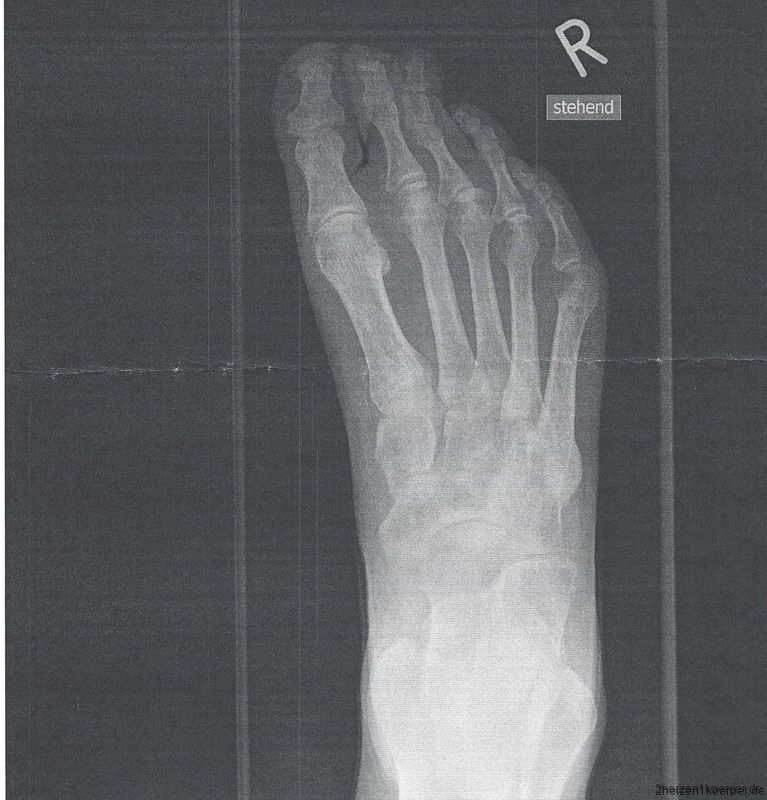

Dies führte mit der Zeit zu einer Verkürzung der Achillessehne, sowie anderer Sehnen und Muskeln. Das Ende vom Lied war, dass ein normaler Gang nicht mehr möglich war. Mit der Zeit wurde diese Verkürzung so schlimm, dass sich die Zehen untereinander stellten. Auf dem Röntgenbild kannst du vielleicht sehen, dass sich alles nach Links neigt.

Es ist sehr schwierig zu gehen, wenn die Zehen untereinander liegen. Hinzu kam außerdem noch, wie oben beschrieben, die schmerzhafte Nervenschädigung. Vielleicht kannst du dir vorstellen, wie sehr ich unter dieser Behinderung litt und bis heute leide.